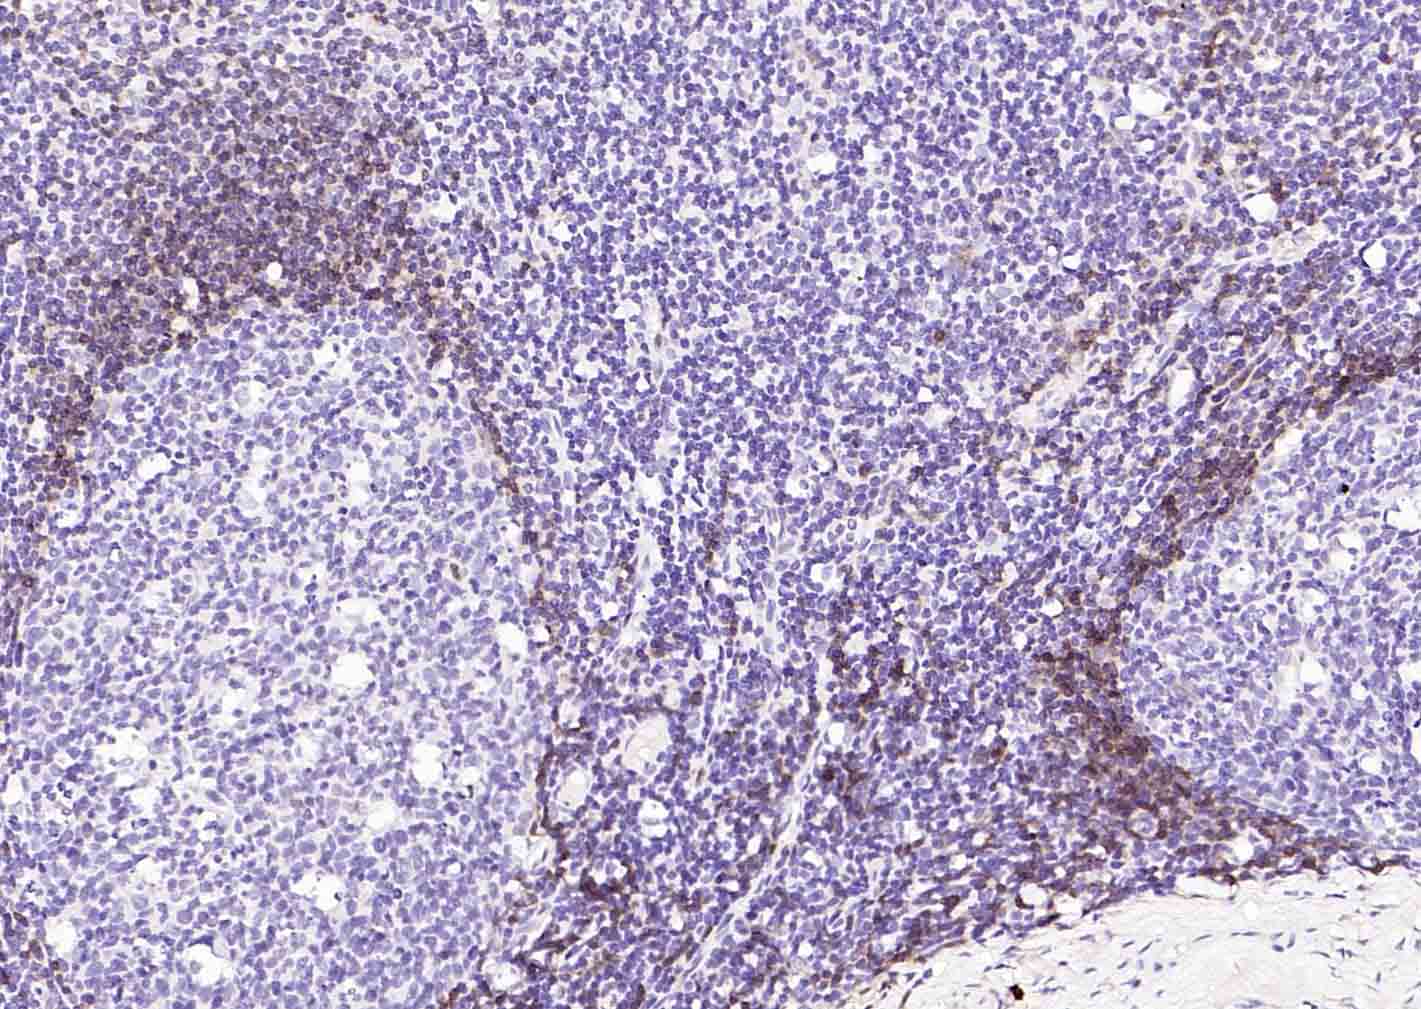

Paraformaldehyde-fixed, paraffin embedded (human tonsil); Antigen retrieval by boiling in sodium citrate buffer (pH6.0) for 15min; Block endogenous peroxidase by 3% hydrogen peroxide for 20 minutes; Blocking buffer (normal goat serum) at 37°C for 30min; Incubation with (Human IgD) Monoclonal Antibody, Unconjugated (bsm-60908R) at 1:50 overnight at 4°C, followed by operating according to SP Kit(Rabbit) (sp-0023) instructionsand DAB staining.